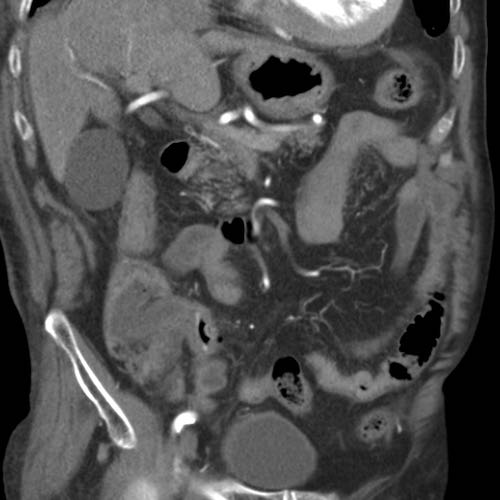

Bệnh nhân nữ 74 tuổi nhập viện với đau bụng dưới sâu kéo dài 3 tuần. Xét nghiệm: bạch cầu 15, CRP 150. Bệnh nhân có tiền sử nhiều lần phẫu thuật phụ khoa.

CT được thực hiện và phát hiện một dị vật dạng xương, với cả hai đầu đều có vẻ xuyên thủng đại tràng sigma.

Siêu âm qua đường âm đạo xác nhận dị vật đi xuyên qua lòng đại tràng sigma, do đó có thể lấy dị vật qua nội soi đại tràng.

Trong quá trình nội soi, xương gà phải được bẻ làm hai phần để lấy ra an toàn. Bệnh nhân hồi phục tốt với sự hỗ trợ của kháng sinh.